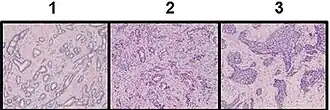

The Nottingham system[12] is recommended for breast cancer grading.[13] The Nottingham system is also called the Bloom–Richardson–Elston system (BRE),[14] or the Elston-Ellis modification[15] of the Scarff-Bloom-Richardson grading system.[16][17] It grades breast carcinomas by adding up scores for tubule formation, nuclear pleomorphism, and mitotic count, each of which is given 1 to 3 points. The scores for each of these three criteria are then added together to give an overall final score and corresponding grade. It is not applicable to medullary carcinomas which are histologically high-grade by definition, while being clinically low-grade if lymph nodes are negative.[18] It is also not applicable to metaplastic carcinomas.[19]

Tubule formation

This parameter assesses what percent of the tumor forms normal duct structures. In cancer, there is a breakdown of the mechanisms that cells use to attach to each other and communicate with each other, to form tissues such as ducts, so the tissue structures become less orderly.

Note: The overall appearance of the tumor has to be considered.[20]

- 1 point: tubular formation in more than 75% of the tumor (it may in addition be termed "majority of tumor")

- 2 points: tubular formation in 10 to 75% of the tumor ("moderate")

- 3 points: tubular formation in less than 10% of the tumor ("little or none")